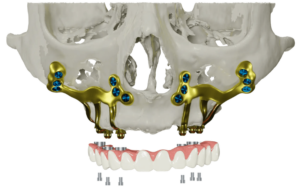

3. Zygomatic Implants in Charlotte, NC

Zygomatic implants are a specialized solution for individuals experiencing severe bone loss in the upper jaw, offering a stable foundation for a permanent upper bridge. Unlike traditional implants, these are considerably longer and are strategically anchored at an angle into the dense zygomatic bone, commonly referred to as the cheekbone.

Zygomatic implants are a highly effective and reliable dental solution offered in Charlotte, particularly for patients requiring upper jaw restorations. At Premier Dental, this advanced procedure is expertly performed by skilled surgeons, delivering numerous key advantages:

- Patients leave with fully functional, fixed teeth on the same day of the procedure.

- Zygomatic implants eliminate the need for upper dentures, providing a more natural and durable alternative.

- By anchoring into the cheekbone, they remove the need for bone grafting, simplifying the process.

- The treatment significantly shortens the timeline for future implants, bridges, or upper jaw restorations.

- Compared to traditional implant options, zygomatic implants are a more cost-effective solution.

- IV sedation ensures a comfortable, stress-free experience throughout the procedure.

- Recovery is fast, allowing most patients to return to daily activities shortly after surgery.

- Extractions and implant placement are usually completed in a single appointment, minimizing inconvenience.